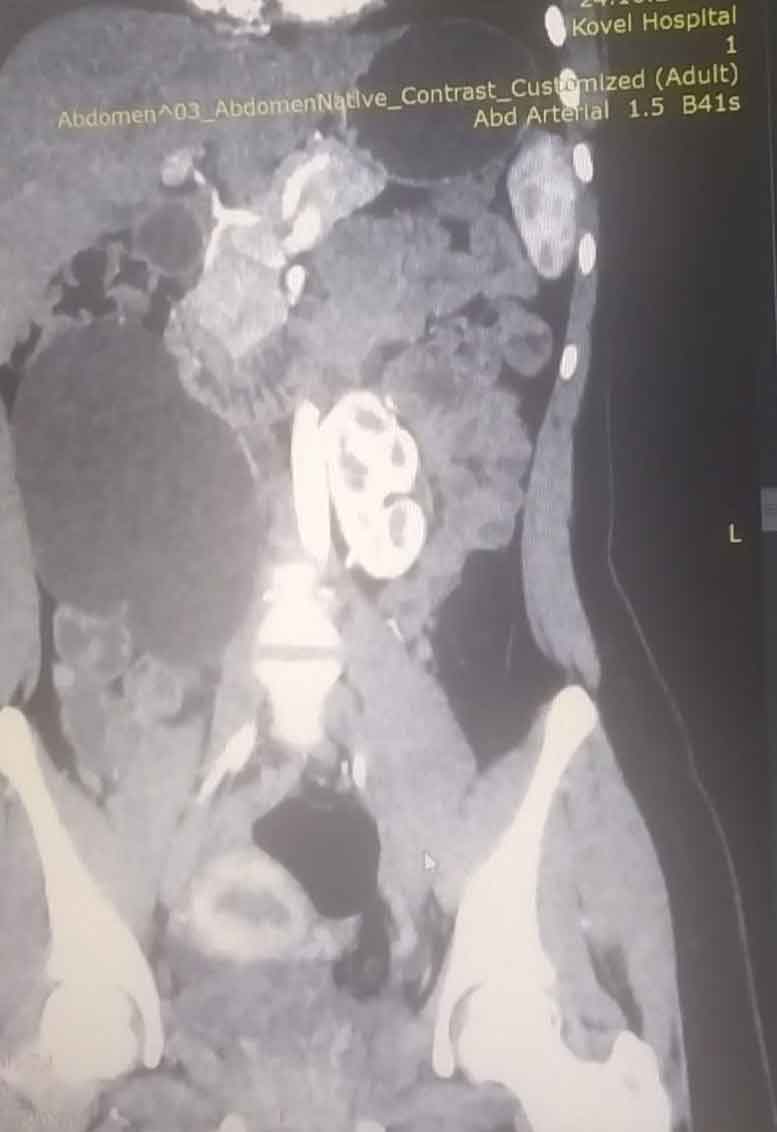

17-річна пацієнтка мала вроджену ваду сечовидільної системи - підковоподібну нирку (зрощення двох нирок). Стан її здоров’я погіршувався упродовж багатьох років, аж поки права половина підковоподібної нирки перестала функціонувати, - повідомляє Ковельське МТМО у Фейсбук

Хвору доставили в лікарню у важкому стані з вираженим больовим синдромом та наявністю гіпертонічного кризу. Через звуження у сечоводі та ускладнення відтоку сечі, об’єм рідини в нирці сягнув критичного рівня. А збільшення її розмірів стало помітним навіть зовні.

Лікарі діагностували термінальний гідронефроз із наслідками, гідронефротичну трансформацію правої половини підковоподібної нирки, вторинну артеріальну гіпертензію.